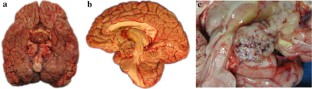

Chordoid gliomas are slowly growing third ventricular tumors that can be challenging to manage clinically. Rapid progression causing death has not been previously reported for this tumor type. We present and discuss a case of chordoid glioma that arose in a 46-year-old female who presented with progressive fatigue, headache, and altered mental status, attributable to severe hydrocephalus caused by a third ventricular mass. She underwent urgent subtotal resection and ventriculo-peritoneal shunt placements. Post-operative MRI noted residual tumor in the anterior resection cavity. An MRI performed 9 weeks later showed substantial progression, with marked tumor enlargement and compression of adjacent hypothalamic structures and the optic chiasm. Despite a course of radiation therapy, the tumor continued to enlarge, and the patient died from tumor progression 7 months after initial presentation. Post-mortem exam demonstrated a mass that expanded the third ventricle and compressed adjacent hypothalamic, thalamic and suprasellar structures. Histologic and immunohistochemical studies confirmed a chordoid glioma and revealed multifocal coagulative necrosis and intravascular thrombosis, which are unusual in this tumor type. Cytogenomic microarray testing revealed numerous DNA copy number abnormalities, many of which had not previously been reported in this tumor. The pathologic and cytogenetic changes may correlate with the aggressive behavior of this chordoid glioma and can be pursued by future investigation of additional cases.

Fig. 1